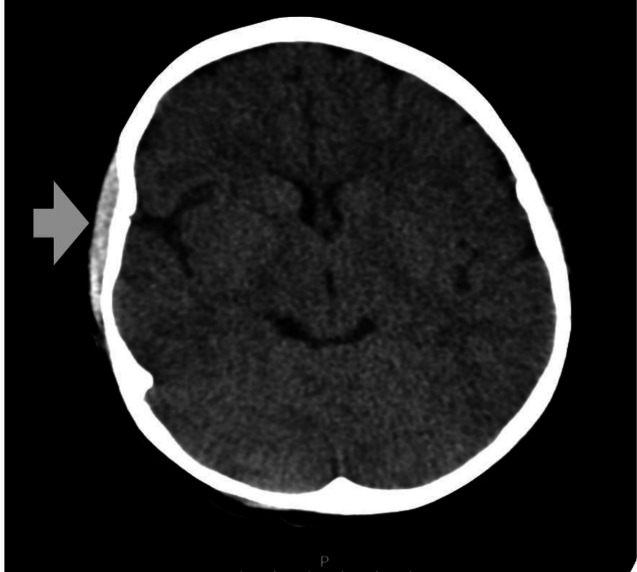

镰状细胞病是一种遗传性的血红蛋白形成疾病,主要影响非洲人、印度人或地中海后裔。由于镰状细胞阻塞小血管,导致组织梗死,这些患者经常发生急性疼痛发作。两名尼日利亚裔儿童在痛苦的危机发作期间出现严重头痛,并伴有头皮肿胀。两例病例的CT成像均显示galgala下血肿,除处理疼痛危机外,还进行了保守处理,结果良好。本报告重点介绍镰状细胞贫血这种罕见并发症的临床表现、诊断方法和治疗。

Sickle cell disease is an inherited disorder of haemoglobin formation, predominantly affecting individuals of African, Indian, or Mediterranean descent. Acute painful episodes frequently occur in these patients due to the blockage of small blood vessels by sickled cells, leading to tissue infarction. Two children of Nigerian descent, presented with severe headaches during a painful crisis episode with associated swelling on their scalps. CT imaging in both cases showed subgaleal haematoma which was managed conservatively in addition to managing the painful crisis with a good outcome. This report highlights the clinical presentation, diagnostic approach, and management of this uncommon complication of sickle cell anaemia.